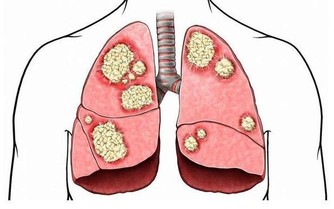

膳食講究平衡,蔬菜水果是我們日常膳食中的重要組成部分,所以,如果平時只愛吃肉,不愛吃蔬菜和水果,就增加了患癌的風險性。研究表明:長期大量攝入紅肉和熟肉製品分別使結腸癌危險增加29%和50%。